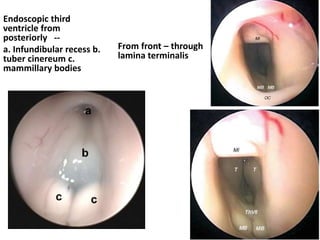

The space between a & oc is Lamina terminalis

Neuroendoscopic view of the third ventricle floor-----Infundibular recess (i), optic chiasm (oc)

and a prominent anterior commissure (a) are seen anterior to the opaque and narrow tuber cinereum (t). B

Neuroendoscopic view of the third ventricle floor in another myelomeningocele patient. A non-transparent

tuber cinereum (t) and a dilated infundibular recess (i) are seen anterior to the mamillary bodies (m). Note to

the vascular structure of the third ventricle floor. cNeuroendoscopic view showing a steep third ventricle

floor in a myelomeningocele patient. A narrow tuber cinereum (t) is visible just anterior to the mamillary

bodies (m). dNeuroendoscopic view through a very narrow prepontine cistern. Note the close proximity of

the basillary artery (ba) and clivus (cl)

Endoscopic third ventricle from

posteriorly -- a. Infundibular

recess b. tuber cinereum c.

mammillary bodies

Endoscopic third

ventricle from

posteriorly --

a. Infundibular recess b.

tuber cinereum c.

From front – through

lamina terminalis

CC corpus callosum, CP choroid plexus, MI massa intermedia, PC posterior commissure, T

thalamus, ThV fl floor of the third ventricle, yellow arrow opening of the Silvius aqueduct, red

asterisk suprapineal recess, white asterisk ( left ) lateral ventricle, white circles foramen of

Monro